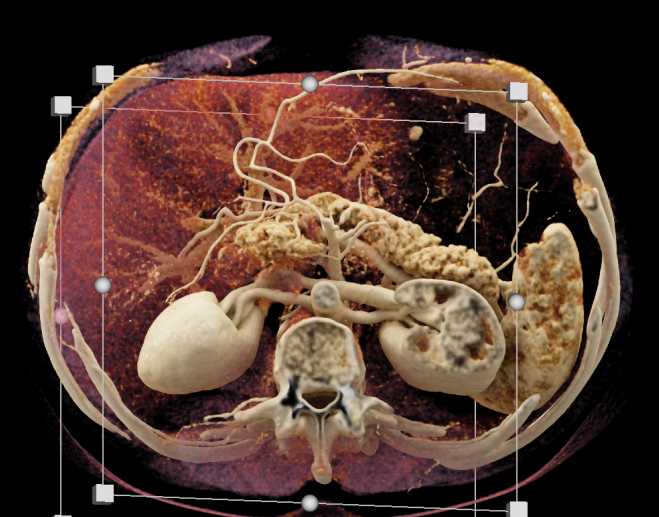

Subtle Neuroendocrine Tumor Body of Pancreas